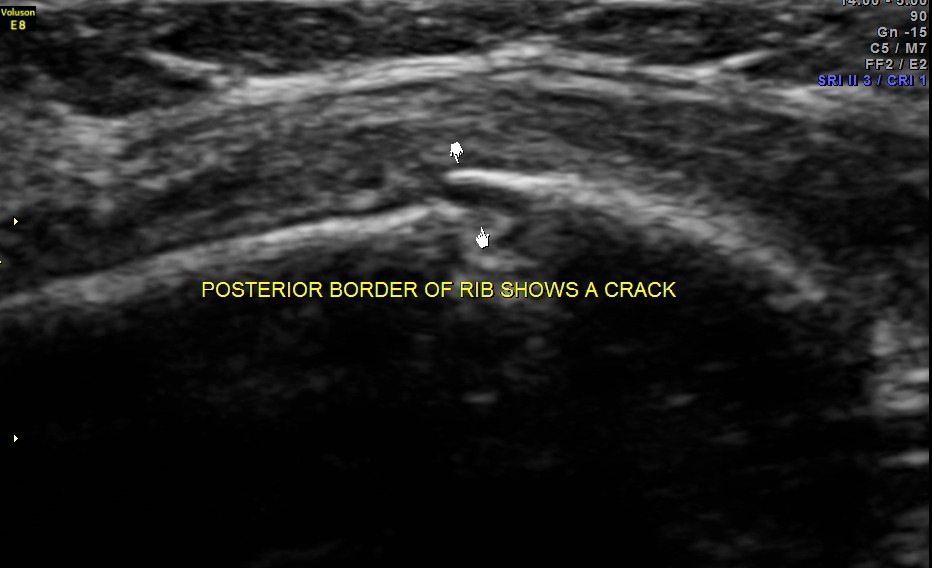

This was a 25 year old lady who fell on her chest while a cow was chasing her . She had persistent severe pain in the left side of the chest. Xray of the rib cage was reported as normal and appeared to be normal.

Scan over the point of maximal tenderness ( over the 6th rib on the left side anteriorly) revealed a crack in the bone on the posterior aspect . Probably as it was not a complete fracture it was missed on the xray.

The images are shown below